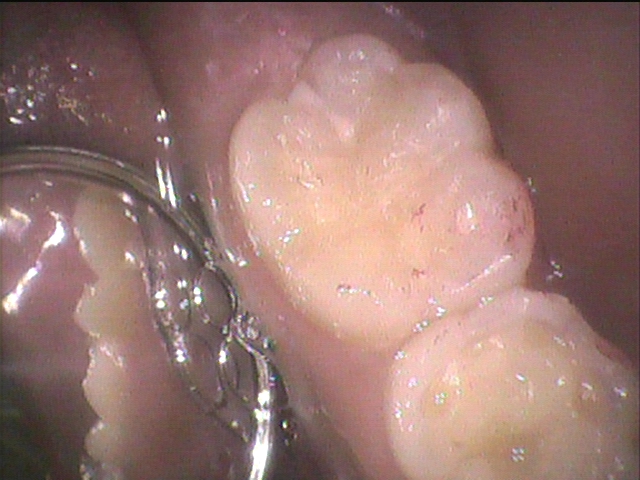

最後にコンポジットレジン充填(今回は咬合力が過度ではなく、範囲も小さいのでトクヤマデンタルのオムニクロマフローを使用)

今回の症例のように小さな虫歯でも意外に中で大きくなっている虫歯(急性虫歯)を見つけるには定期的な検診が有効です。